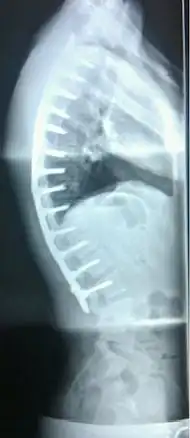

Surgery

In severe or extreme cases, patients may be treated through an extensive surgical procedure in an effort to prevent the disease from worsening or harming the body. The skeletal deformity caused by Scheuermann's disease can be corrected or partially corrected with surgical procedures, almost all of which include multi-level spinal fusion and hardware instrumentation, i.e., rods, pedicle screws, etc. It is important to realize the surgery aims to reduce pain, and not cosmetic defect. As always, surgical intervention should be used as a last resort once conservative treatment fails or the patient's health is in imminent danger as any surgical procedure is not without risk. However, the chances of complication are relatively low, and the surgeries are often successful.

There are two primary surgical techniques to correct kyphosis: posterior-only fusion and anterior/posterior fusion. While debate lingers over which surgical approach is optimal, several studies published since 2018 suggest treatment trends are favoring posterior-only fusion.[17][18][19]

The classic surgical procedure entails entering two titanium rods, each roughly 1.5 feet (0.46 m) long (depending on the size of the kyphosis) into the back on either side of the spine. Eight titanium screws and hardware are drilled through the bone to secure the rods onto either side of the spine. On the internal-facing side of the spine, ligaments (which can be too short, pulling the spine into its abnormal shape) must be surgically cut or released, not only stopping part of the cause of the kyphosis, but also allowing the titanium rods to pull the spine into a more natural position. The damaged discs between the troubled vertebrae (wedged vertebrae) are normally removed and replaced with bone grafting from the hip or other parts of the vertebrae, which once healed or "fused" will solidify. The titanium instrumentation holds everything in place during healing. The patient can expect to remain in hospital for a minimum of a week, and possibly longer. They may then be required to wear a brace for several months more to ensure the spine heals appropriately. The titanium instrumentation may stay in the body permanently, or be removed years later. Patients who have undergone such surgery may need physical therapy to manage pain and mobility. Recovery can be prolonged: typically patients are not allowed to lift anything above 5–10 pounds (2.3–4.5 kg) for 6 months to 1 year, and many are out of work for 3 to 6 months. However, once the fusion is solidified, most patients can return to their usual lifestyle within 1–2 years.

Spinal fusion for kyphosis and scoliosis is an extremely invasive surgery. The risk of complications is estimated to be about 10%. Possible complications may be inflammation of the soft tissue or deep inflammatory processes, breathing impairments, bleeding and nerve injuries, or infection. As early as five years after surgery around 5% require reoperation and long-term issues remain unclear.[20][21]